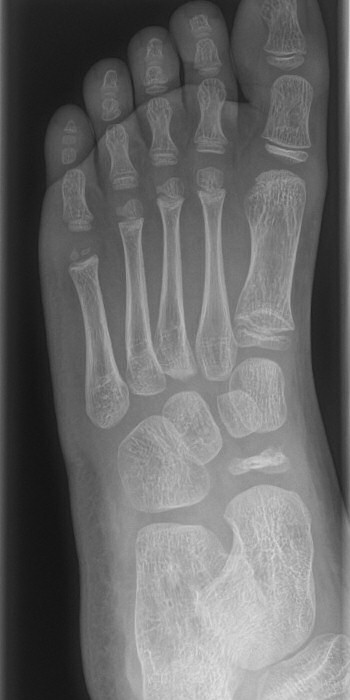

Slätröntgen som visar skleros, fragmentering och tillplattat os navikulare [1, 2] resp. huvud av metatarsalben [1].

Första bilden visar Köhler typ 1 med tillplattat os navikulare, andra bilden resttillstånd efter Köhler typ 2 i kaput metatarsale 2.